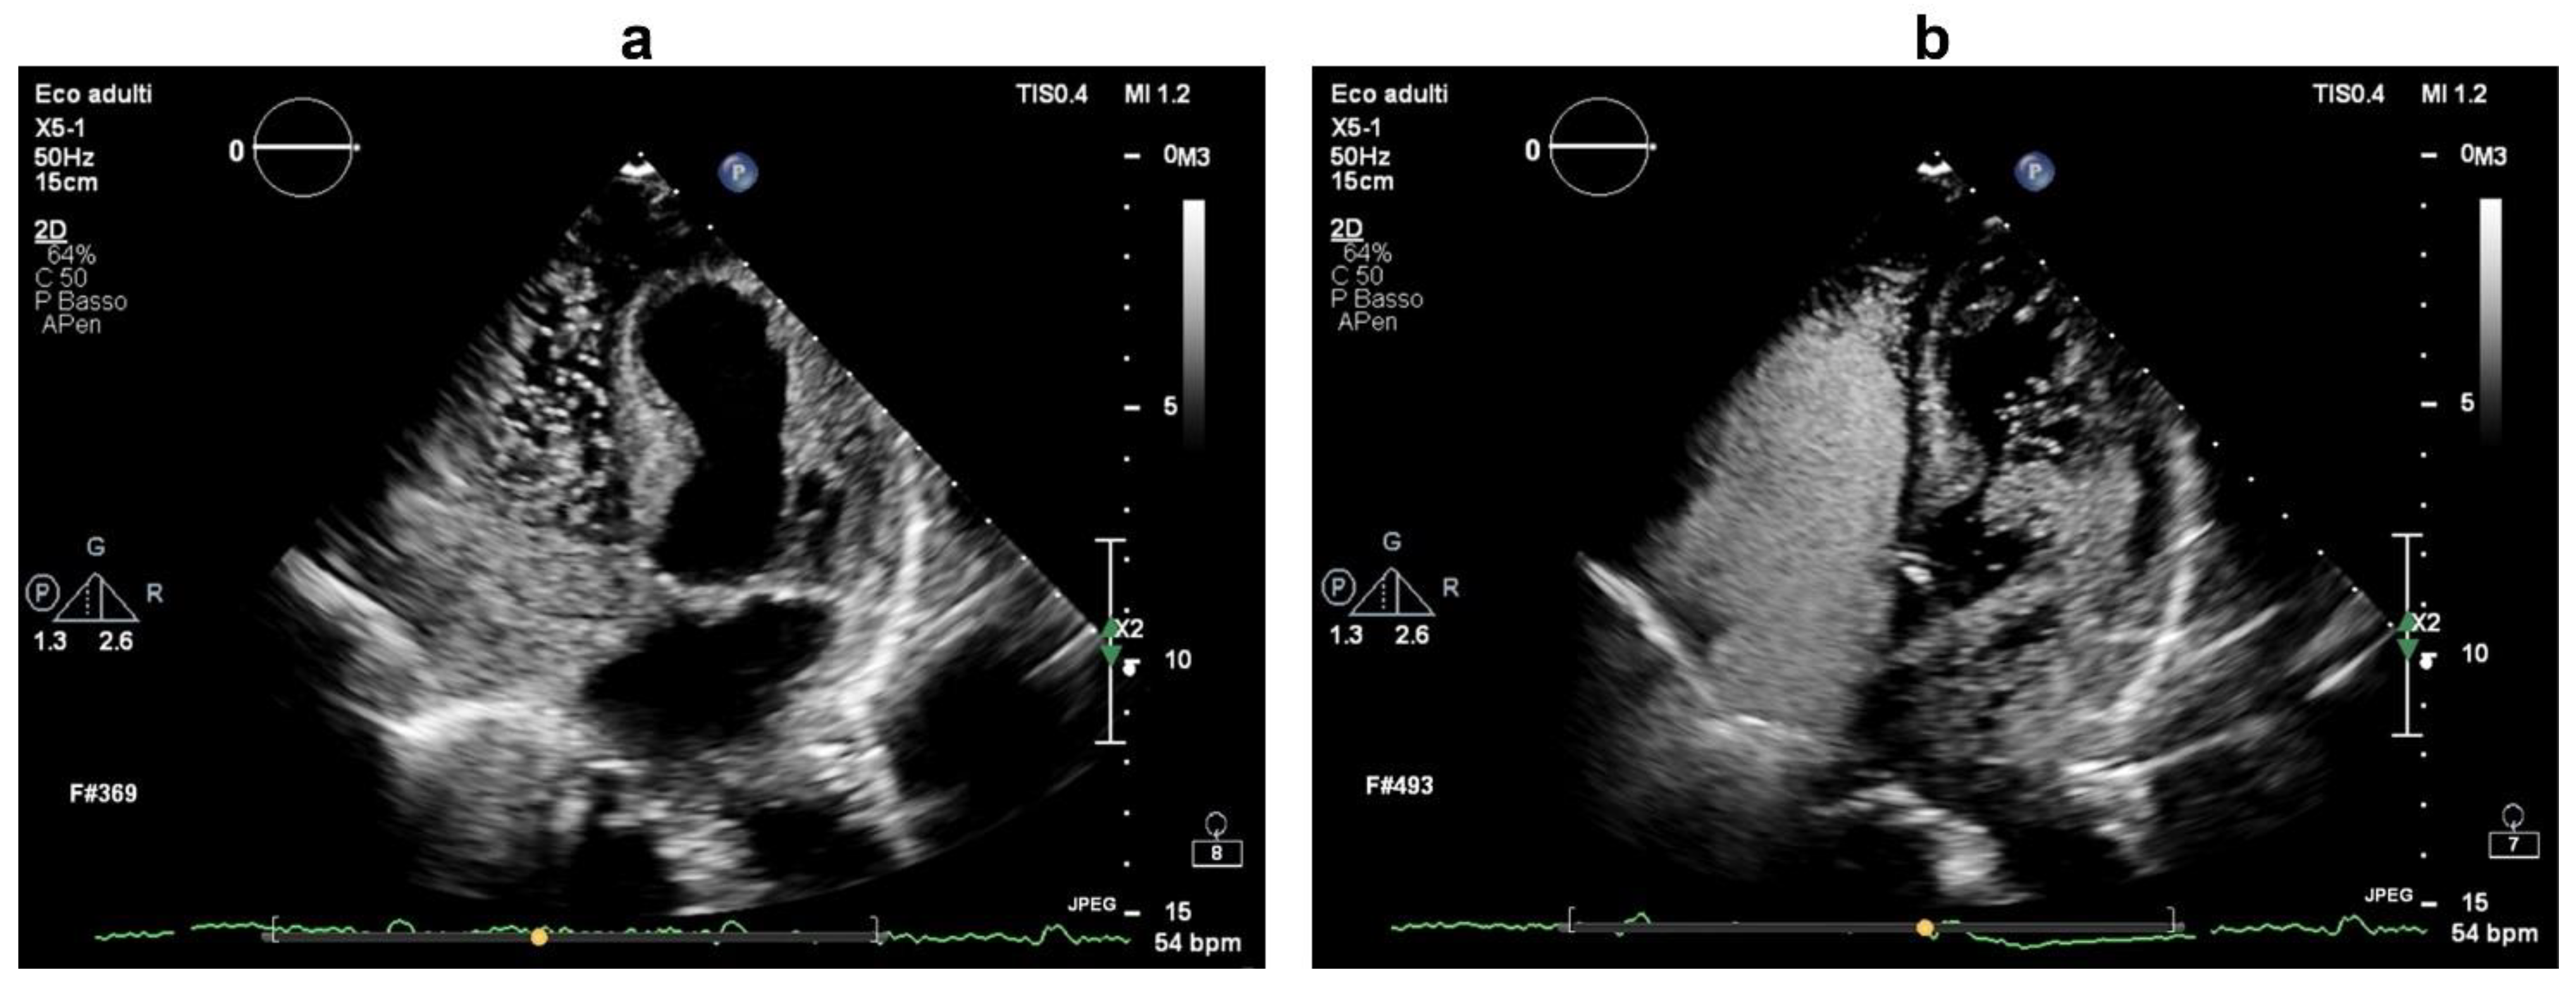

A complete stroke work-up was subsequently performed. Carotid ultrasound revealed only small (<30%) fibrocalcific plaques of the internal and external carotid arteries. On a seven-day continuous electrocardiographic monitoring, there was evidence of sinus bradycardia (mean heart rate of 50 bpm) with no pathological pauses or significant tachyarrhytmias. On transthoracic echocardiography, the ventricular septum was mildly hypertrophic, the left atrium was moderately enlarged, there was mild-to-moderate tricuspid regurgitation with an increased systolic pulmonary arterial pressure (45 mmHg), but no visible intracardiac shunt. Based on the close temporal relationship between the development of neurological dysfunction and central venous catheterization, there was a strong suspicion of paradoxical embolism, and more specific investigations were ordered. Transcranial Doppler ultrasound with agitated saline was negative at rest, but, during a Valsalva manoeuvre, it documented a “shower” appearance of microembolic signals over the middle cerebral artery, indicating a high-grade right-to-left shunt (Figure 2). Transthoracic ecocardiography with agitated saline achieved complete opacification of the right heart at rest; during a Valsalva manoeuvre, it visualized more than 20 bubbles in the left heart chambers within three cardiac cycles from complete opacification of the right atrium (Figure 3, Supplementary Video S1), establishing the diagnosis of a high-grade right-to-left intracardiac shunt. The intermittent nature of the right-to-left shunt was consistent with a PFO.

Figure 3. Transthoracic echocardiogram (apical four-chamber view) during intravenous infusion of agitated saline associated with a Valsalva manoeuvre. In (a), saline contrast can be seen filling the right heart chambers. In (b), numerous microbubbles (>20) can be visualized in the left heart chambers within three cardiac cycles from complete opacification of the right atrium, demonstrating a high-grade right-to-left intracardiac shunt consistent with patent foramen ovale.